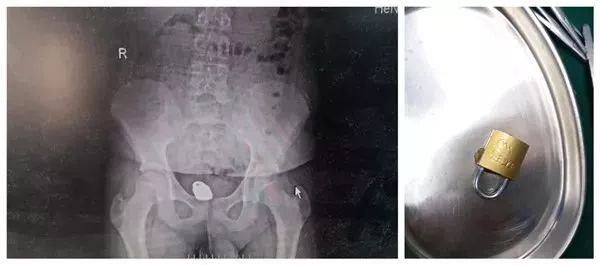

2019年6月,一位父亲就带着12岁的儿子前来河南省直第三人民医院消化病诊疗中心就诊。

男孩用恐惧加不好意思的表情诉说着自己的情况:他在家没事干,就不小心把一把锁塞进肛门,随后感到有一种坠胀感,试着用手指扣出,非但没有成功,反而往上移动许多。随后大便就开始出血,实在没有办法就告知了父亲,紧急来到了医院。医生在排除穿孔后,当晚加班手术顺利取出。